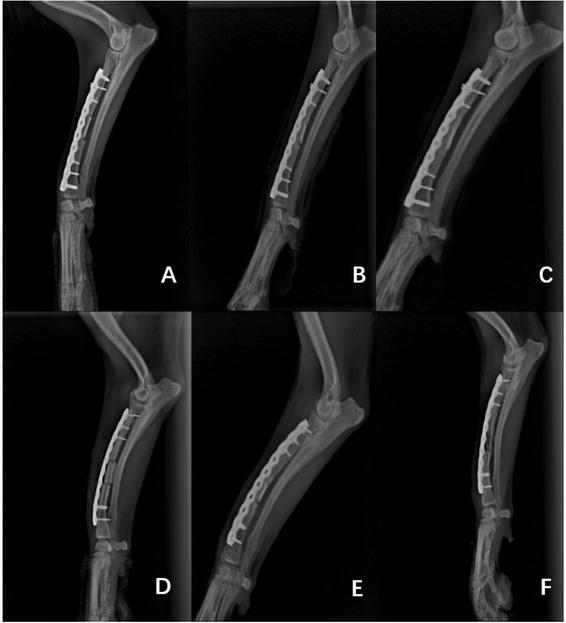

At 12 weeks, the bone healing boundary was disappearing more quickly in group T dogs than in their group C counterparts. X-ray and histological examinations showed that the cortical repair of group T subjects was complete and the bony plate arrangement was more regular than that in group C. The levels of bone biochemical markers also proved that the healing state of group T was better.